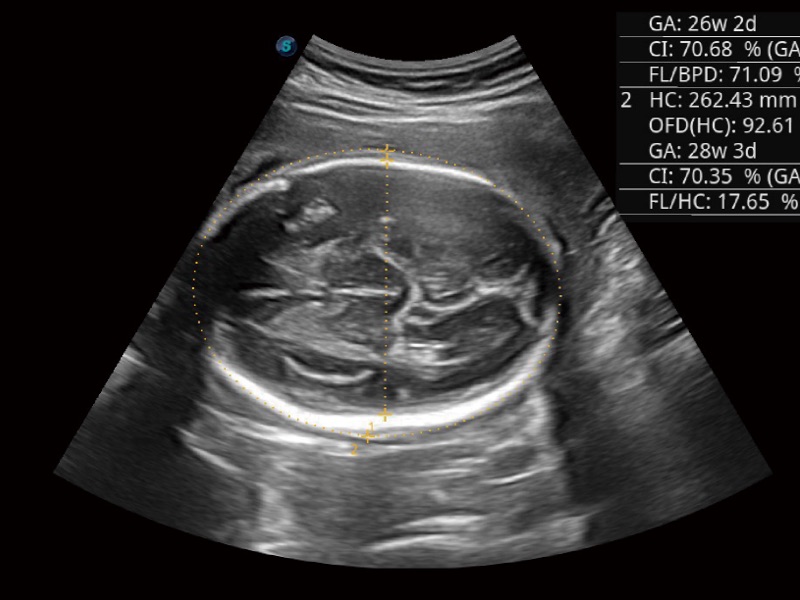

婦產(chǎn)科應(yīng)用